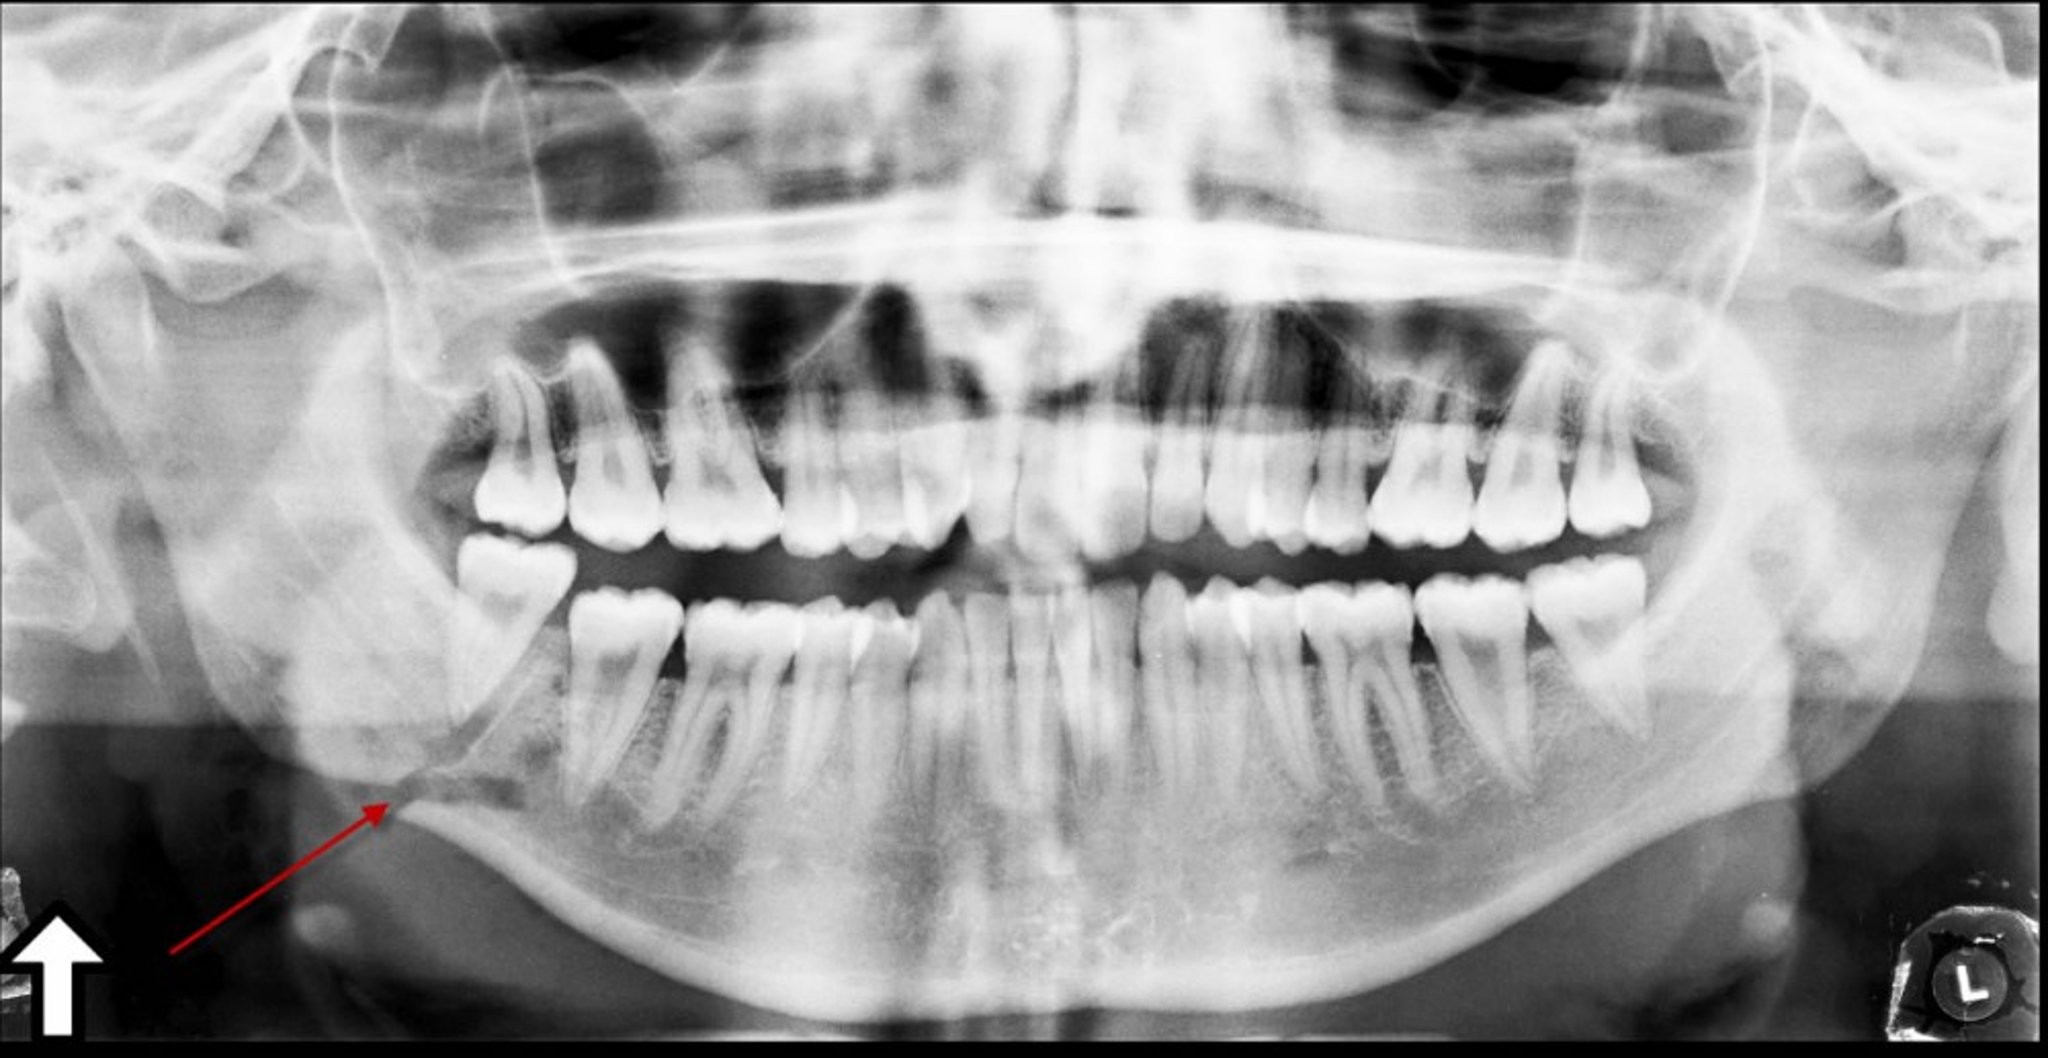

Fracture of the Angle of the Mandible

This panoramic x-ray shows a lucency (arrow) at the angle of the mandible, representing a fracture.